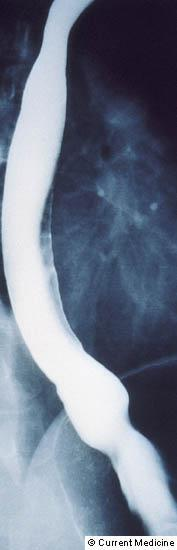

Xəstəliyin dəqiqləşdirilməsi üçün kontrastlı Rentgenoloji müayinə, KT və çox ehtiyatla endskopiya edilməlidir.

- Kontrastlı rentgenoqrafiya - dəqiqləşdirici müayinə üsuludur.

- KT və endoskopik USM - etioloji diaqnostika (divararalığının və QB-nun xəstəliklərinin diaqnostikası) üçün olduqca vacibdir.

- Kontrastlı Rentgenoloji müayinədə və ya KT-də divertikul görünməsi

Diaqnozun dəqiqləşdirilməsi üçün kontrastlı şüa diaqnostikası üsulları (Rh-qrafiya və ya KT) və endoskopiya aparılmalıdır.

- Kontrastlı Rh-qrafiya - dəqiqləşdirici müayinə üsuludur.

- Kontrastlı müayinələrdə (Rh-qrafiya, KT) divertikul görünməsi